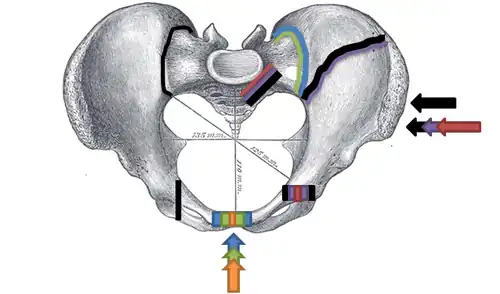

Le bassin est une structure osseuse formant un anneau en entonnoir, particulièrement stable dans son intégrité. Les éléments osseux sont maintenus par deux systèmes principaux de ligaments : en avant celui de la symphyse pubienne, et en arrière celui de l'articulation sacro-iliaque, les deux réunis par les ligaments du plancher pelvien.

En fonction des forces appliquées sur le bassin, trois mécanismes sont décrits :

- La compression antéro-postérieure : elle endommage d'abord les ligaments de la symphyse pubienne, suivi de la rupture des ligaments du plancher pelvien (ligaments sacro-iliaques), et enfin fracture des deux cadres obturateurs.

- La compression latérale : elle se traduit par des fractures du cadre obturateur, de l'aile iliaque (dite fracture de Malgaigne), ou d'un aileron sacré (dite fracture de Voillemier[9]).

- La compression verticale : un choc asymétrique sur une moitié d'un pelvis (chute de hauteur ou collision à grande vitesse) peut entrainer un cisaillement avec déplacement vertical du même type de lésions rencontrées dans les compressions latérales.

Un quatrième mécanisme est dit « complexe ou combiné », lorsqu'il associe plusieurs des mécanismes précédents.

Dans le cas de fracture du bassin par compression antéro-postérieure, dite open book « à livre ouvert », la symphyse pubienne peut se rompre et s'écarter en s'ouvrant comme un livre. La cavité du bassin augmente de volume, et ne joue plus son « rôle tampon » en restant fermée. Le risque principal est alors l'hématome du rétropéritoine qui peut aller jusqu'à 4 litres de sang, avec déséquilibre hémodynamique et état de choc hypovolémique[4],[11].